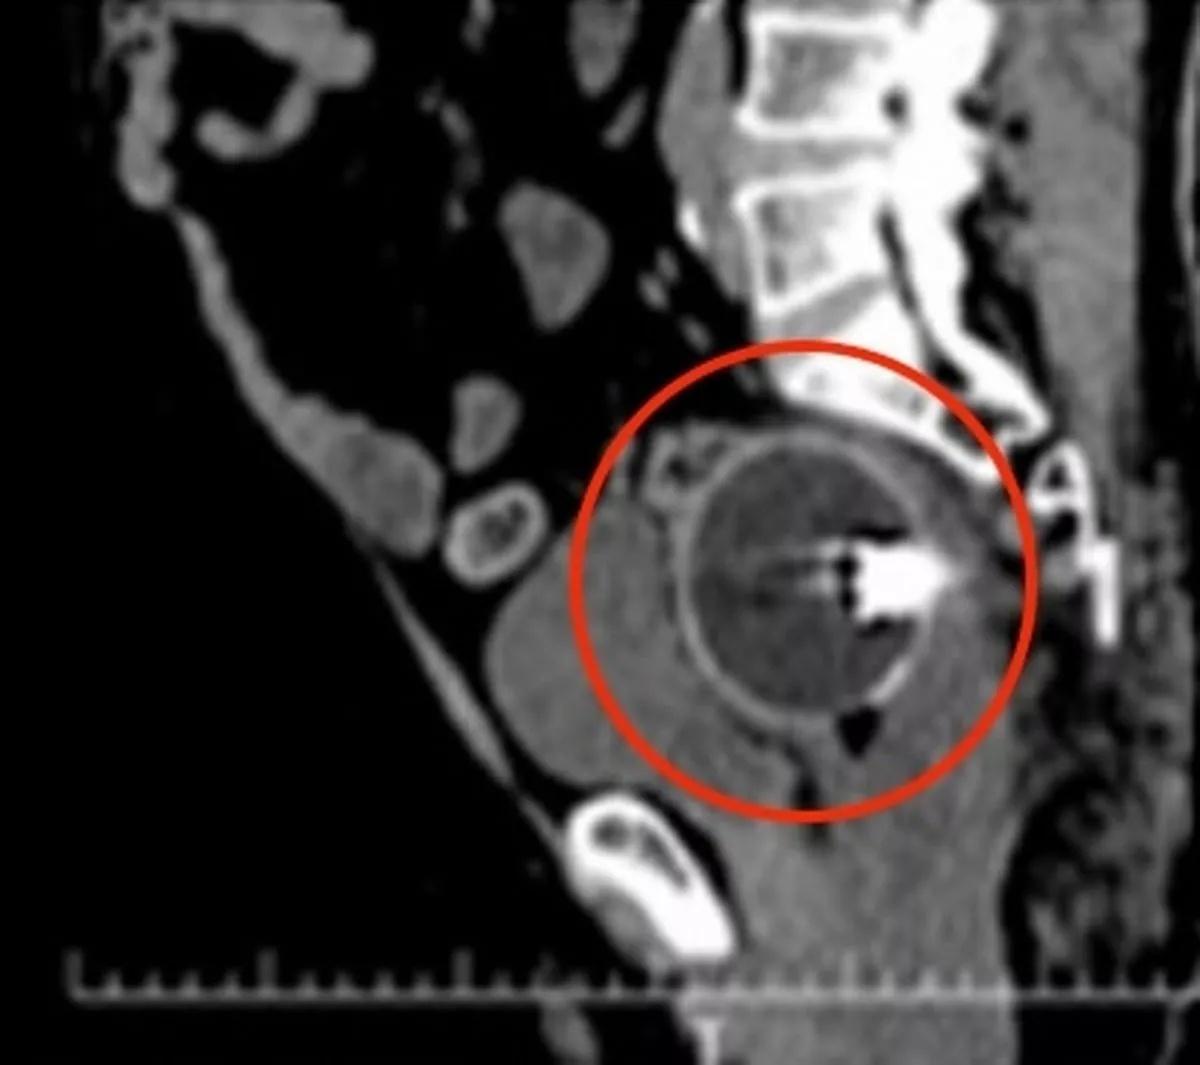

外國一名62歲男子,將一個直徑6.5厘米的兒童閃光球塞入肛門,結果卡在直腸裡無法取出,他難抵臀部劇疼於是到醫院求助。綜合報道,男子到醫院後,亦承認肛門裡卡有異物,經過檢查,發現一個透明的閃光球,兩側各有一張卡通臉。它還包含較小的滾珠軸承和紅色液體。肛門檢查顯示,球卡在男子的直腸內,距離肛門約 7 厘米處。醫生作進一步檢查後,發現球體卡住的區域,血流量高於其他部位,且有黏膜腫脹、出血等情況。

閃光球在刺穿後取出

為了順利取出閃光球,醫生決定先替男子進行全身麻醉,再將閃光球刺破,待裡面的液體、空氣排出,再將「漏氣」球體拉出來。手術結果順利進行,閃光球已被取出,雖然男子的直腸有侵蝕性出血,不過活動性出血已經停止,肛門、腸道也沒有穿孔的情況發生。這宗病例已在記錄於科學和醫學期刊「ScienceDirect」。